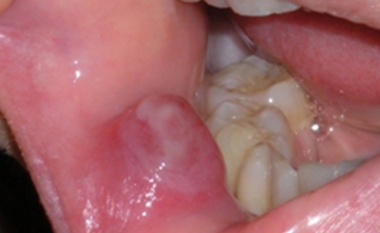

Een van de meest voorkomende afwijkingen is het opgezwollen speekselkliertje in de onderlip, de mucocoele. De mucocoele schemert vaak een beetje blauw. Bij doorprikken komt er wat taai ingedikt speeksel uit. De behandeling bestaat uit een chirurgische verwijdering. Deze kan onder plaatselijke verdoving plaatsvinden.